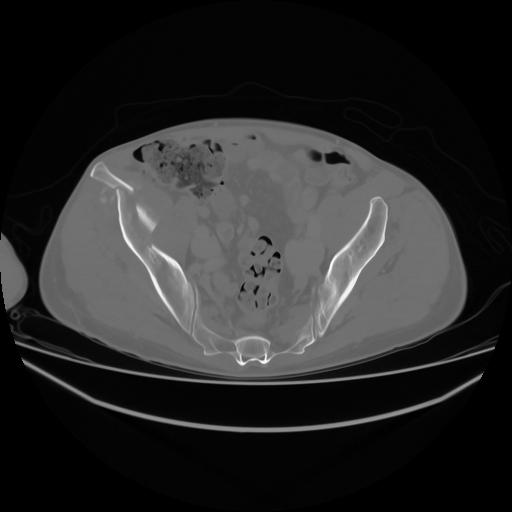

4 CUERPO,CE,Axial,3.0,CUERPO,,